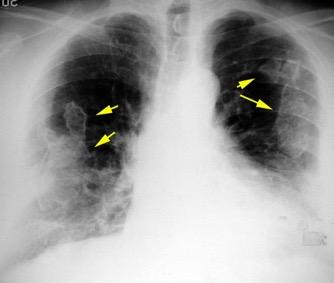

Tromboembolismo pulmonar.

Frecuencia del derrame:

Rx: 32%. TC: 47%

Unilateral. 85%

< 1/3 del hemitórax: 90%

Todos exudados

58% con eritrocitos

21% tabicación lo que causa demora en el diagnóstico

TEP. Empiema pleural. Atelectasia redonda

Porcel JM et al. Analysis of pleural effusions in acute pulmonary embolism: radiological and pleural fluid data from 230 patients. Respirology 2007/ Iguchi T et al. Desquamation of the subpleural lung parenchyma caused by empyema after pulmonary embolism: A case report. Respirol Case Rep. 2022 .

Derrame pleural 43-48% de pacientes con embolismo.

< 1/3 de hemitórax: 90%.(puede haber en lado opuesto).

Siempre exudados.

75% de los pacientes con TEP y derrame pleural tienen dolor pleurítico.

La disnea desproporcionada